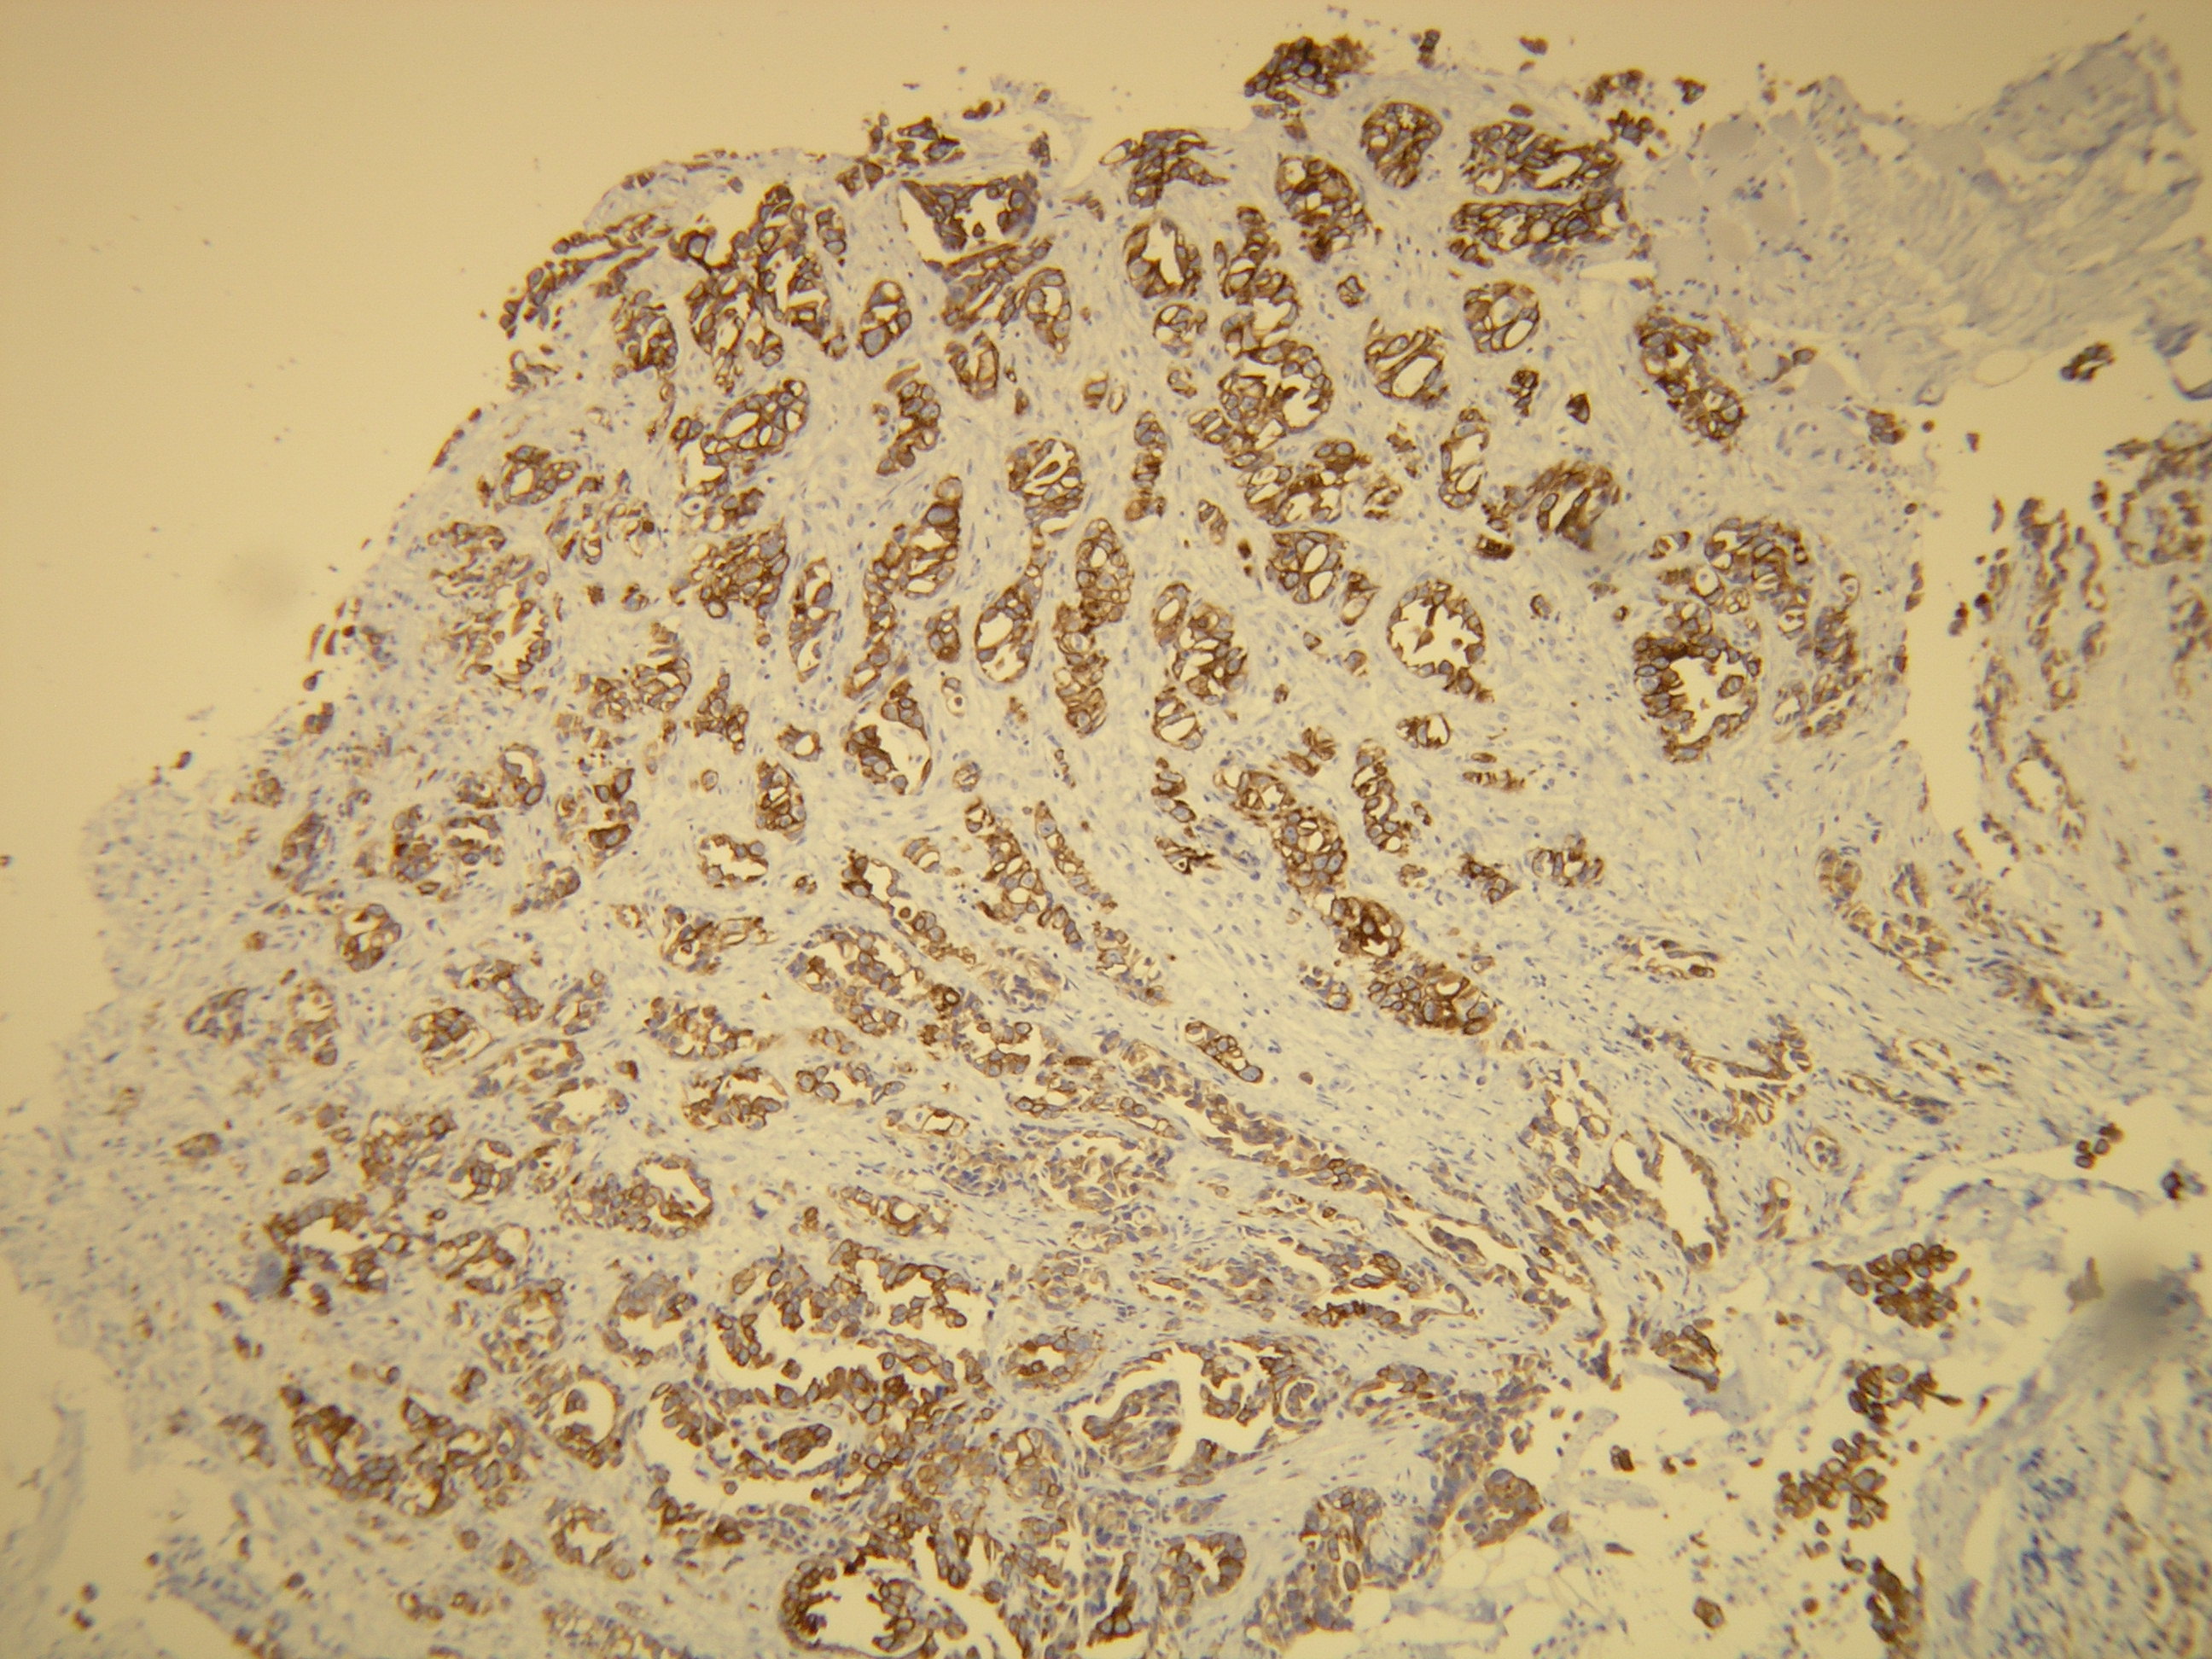

Anti-Cytokeratin 7

Peptid derivovaný z N-koncovej sekvencie ľudského cytokeratin 7. Protilátka rozpoznáva epitop umiestnený medzi Ala22 - Ser38.

Aplikácia

IHC-P, riedenie 1:100

db051 db051b db051c